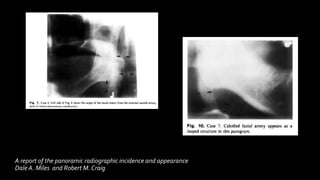

Calcified facial artery

▪ Facial artery calcification was first demonstrated on intraoral

A report of the panoramic radiographic incidence and appearance

Dale A. Miles and Robert M. Craig